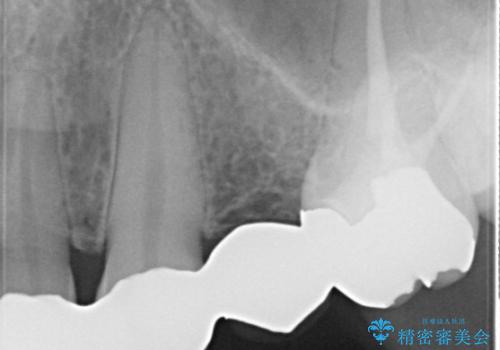

- 保険治療で装着されたかぶせ物と詰め物を変更したいとのことで来院されました。

自然なオールセラミックへ変更することとなりました。

金属を使わないセラミックへ変更することで、自然な見た目になるとともに、ぴったりとした精度の高いかぶせ物を装着することができました。